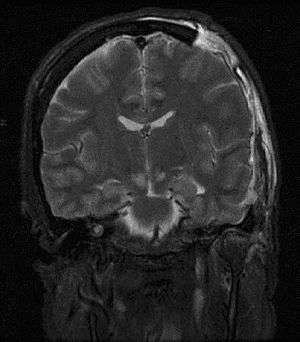

In tonsillar herniation, also called downward cerebellar herniation,[4] transforaminal herniation, or "coning", the cerebellar tonsils move downward through the foramen magnum possibly causing compression of the lower brainstem and upper cervical spinal cord as they pass through the foramen magnum.[5] Increased pressure on the brainstem can result in dysfunction of the centers in the brain responsible for controlling respiratory and cardiac function. The most common signs are intractable headache, head tilt, and neck stiffness due to tonsillar impaction. The level of consciousness may decrease and also give rise to flaccid paralysis. Blood pressure instability is also evident in these patients.[9]

Tonsillar herniation of the cerebellum is also known as a Chiari malformation (CM), or previously an Arnold-Chiari malformation (ACM). There are four types of Chiari malformation, and they represent very different disease processes with different symptoms and prognosis. These conditions can be found in asymptomatic patients as an incidental finding, or can be so severe as to be life-threatening. This condition is now being diagnosed more frequently by radiologists, as more patients undergo MRI scans of their heads, especially upright MRI, which is more than twice as sensitive for detecting this condition.[12] Cerebellar tonsillar ectopia (CTE) is a term used by radiologists to describe cerebellar tonsils that are "low lying" but that do not meet the radiographic criteria for definition as a Chiari malformation. The currently accepted radiographic definition for a Chiari malformation is that cerebellar tonsils lie at least 5mm below the level of the foramen magnum. Some clinicians have reported that some patients appear to experience symptoms consistent with a Chiari malformation without radiographic evidence of tonsillar herniation. Sometimes these patients are described as having a 'Chiari [type] 0'.

For further evaluation of tonsillar herniation, CINE flow studies are used. This type of MRI examines flow of CSF at the cranio-cervical joint. For persons experiencing symptoms but without clear MRI evidence, especially if the symptoms are better in the supine position and worse upon standing/upright, an upright MRI may be useful.[2]